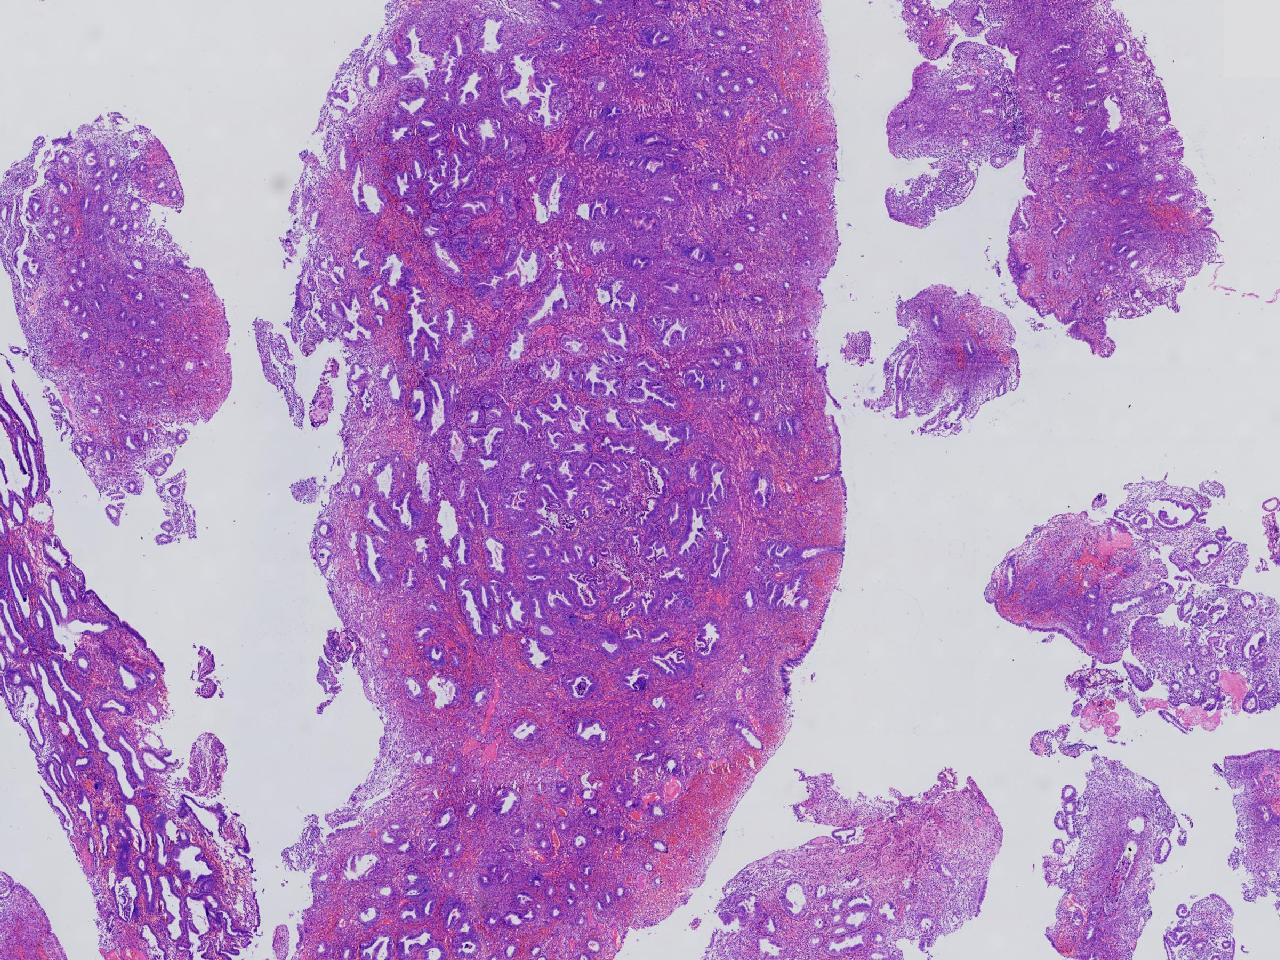

请教。1.有没有非典? 2.内膜是什么变化?

女,50岁,彩超示:粘膜厚度1.1cm。宫腔可见数个高回声,提示宫腔息肉。

子宫内膜+内膜息肉

灰粉色不整形软组织多块,3X3X2厘米。

子宫内膜息肉。

没有非典。

无非典型性子宫内膜增生,子宫内膜息肉

无非典内膜伴息肉。